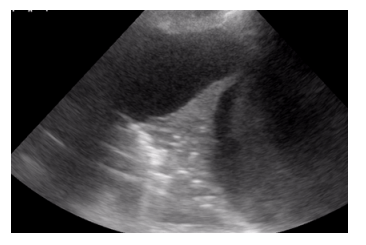

O exame físico do hemitórax esquerdo de um paciente internado na enfermaria de clínica médica, com dispneia, revelou: ausculta abolida, frêmito toracovocal abolido, percussão maciça. O POCUS realizado em transição toracoabdominal evidencia a imagem a seguir.

Enunciado 3526396-1

Com base nessa situação hipotética, é correto afirmar que a alteração patológica percebida no exame físico e no exame complementar trata-se de